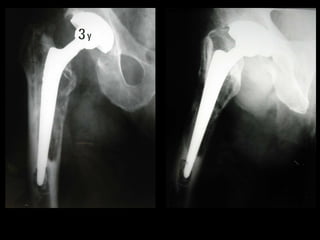

Paprosky 1

Follow up a 3

anni